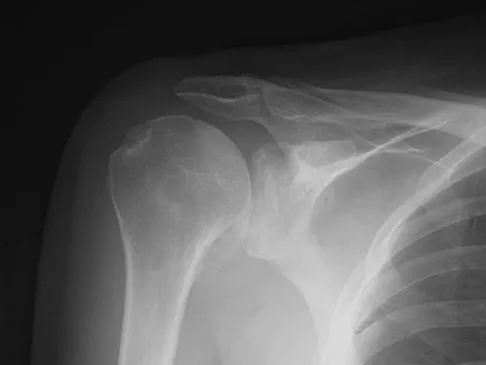

Figure 4a shows the radiograph of a 20-year-old man who has an injury to the right shoulder. Figure 4b shows an arthroscopic view (posterior portal). The arrow points to a

Explanation

The radiograph shows an anterior dislocation of the shoulder. A frequently encountered sequela of this is a compression fracture of the posterolateral humeral head, commonly referred to as a Hill-Sachs defect. The arthroscopic view of the glenohumeral joint visualizes the posterior aspect of the humeral head. In the image, the area devoid of cartilage to the right is the bare area. The indentation seen to the left is a Hill-Sachs defect. Matsen FA, Thomas SC, Rockwood CA, et al: Glenohumeral instability, in Rockwood CA, Matsen FA (eds): The Shoulder, ed 2. Philadelphia, PA, WB Saunders, 1998, pp 611-754.